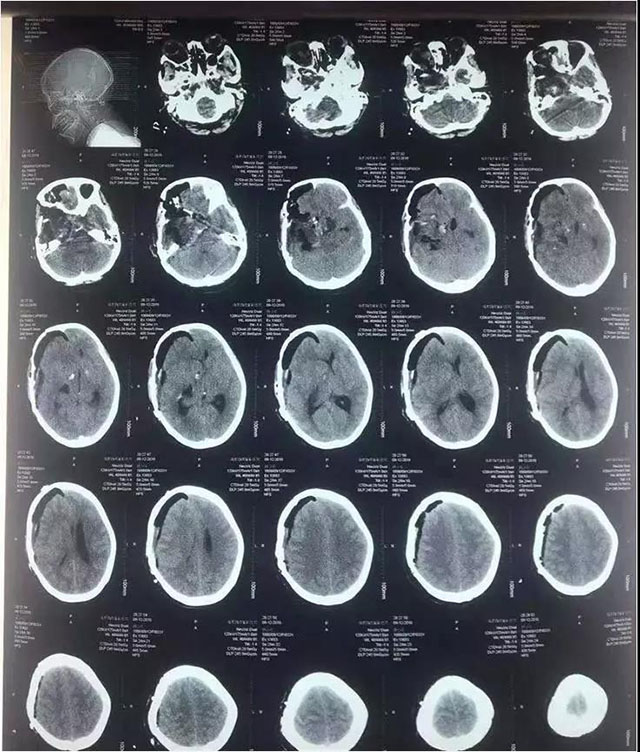

中脑海绵状血管瘤手术

术前

术后